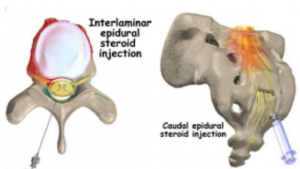

- 脊椎硬膜外注射

脊椎硬膜外注射